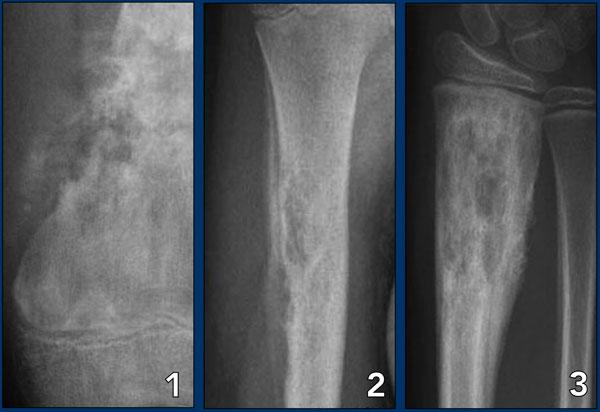

Images

- Osteosarcoma

- Osteomyelitis

- Eosinophilic granuloma

Nhiễm trùng và u hạt tăng bạch cầu ái toan

Nhiễm trùng và u hạt tăng bạch cầu ái toan là những trường hợp ngoại lệ vì chúng là các tổn thương lành tính nhưng có thể bắt chước một khối u xương ác tính do hành vi sinh học xâm lấn của chúng.

Những tổn thương này có thể có bờ không rõ ràng, nhưng cũng có thể thấy hình ảnh phá hủy vỏ xương và phản ứng màng xương kiểu xâm lấn.